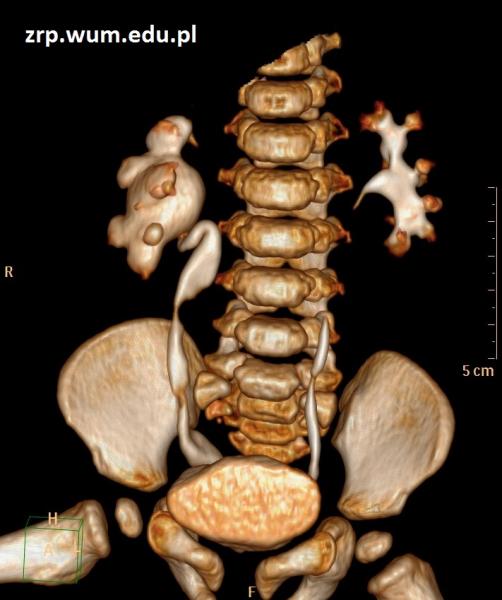

Przypadek 55: 16-letni chłopiec z podejrzeniem guza śródpiersia górnego, wykrytego w kontrolnym badaniu echokardiograficznym.

Rozpoznanie: Na zdjęciu RTG klatki piersiowej stwierdzono poszerzenie cienia śródpiersia po stronie lewej, w rzucie lewej wnęki. W trakcie dalszej diagnostyki rozpoznano chłoniaka.